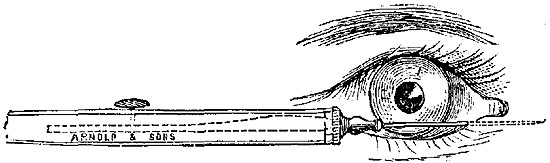

OPERATIONS ON THE EYE AND ITS APPENDAGES. | |

| Entropium and Ectropium—Trichiasis—Tarsal Tumours—On Lachrymal Organs—Mr. Bowman's Operation—Pterygium—Strabismus, convergent and divergent—Paracentesis of the Anterior Chamber—Operations for Cataract by Displacement, Solution, and Extraction—Various methods of Extraction—Operations for Artificial Pupil—Iridesis—Corelysis—Iridectomy—Excision of Staphyloma—Excision of Eyeball, | 151-174 |